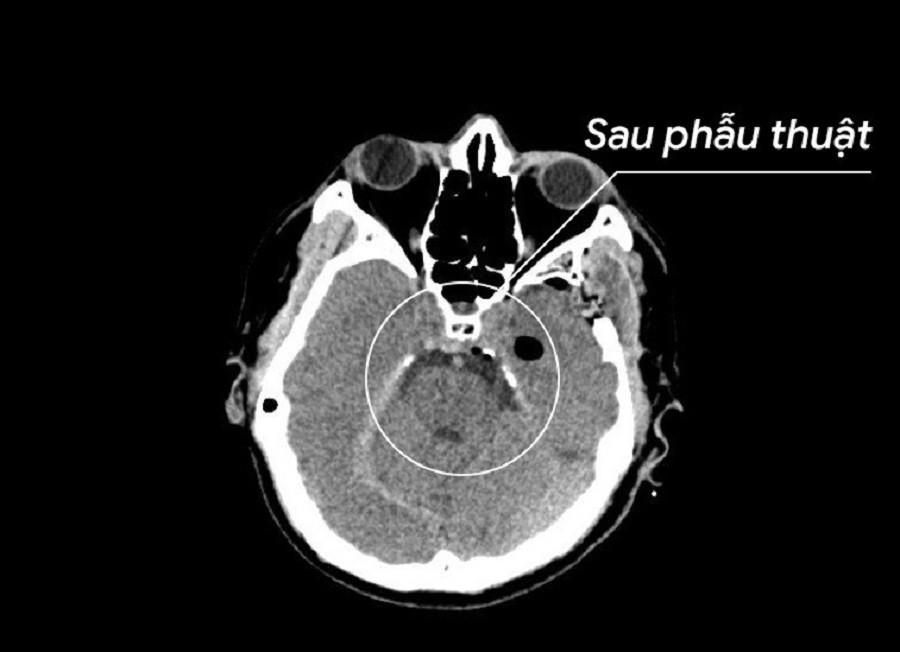

![]() |

| Kết quả kiểm tra sau phẫu thuật, khối u đã được loại bỏ triệt để, sức khỏe bệnh nhân bình phục tốt |